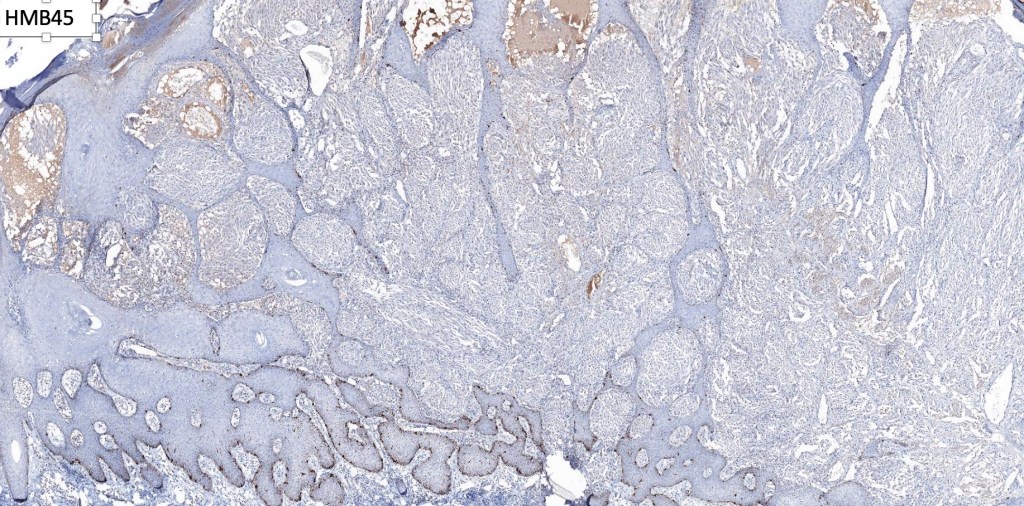

•S100, MART1 & SOX10 +ve, HMB45 +ve (superficially & lost progressively with depth), p16 +ve, p21 +ve